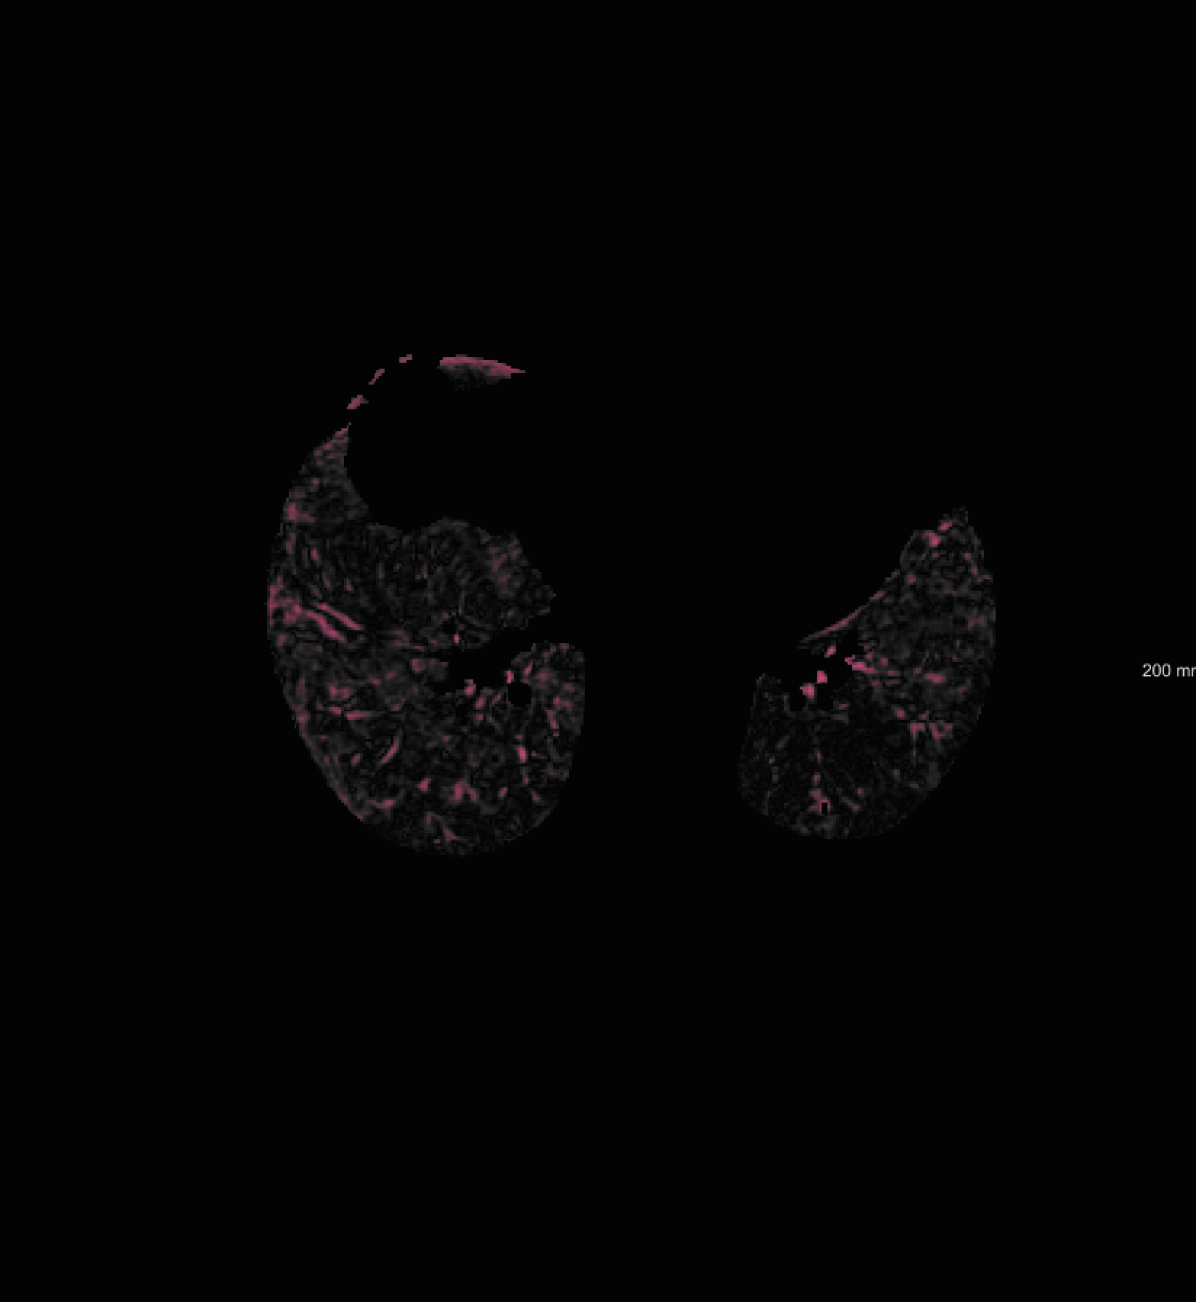

respiratory motion: We simulate respiratory motion with three components similar to Hub et al. (2009) as follows: Expansion of the chest in the transversal plane with a maximum scaling factor of 1.12; Transition of the diaphragm in cranio-caudal direction with a maximum deformation of ; Random deformation using the single frequency method. In order to locate the diaphragm, an automatically detected lung mask is used.